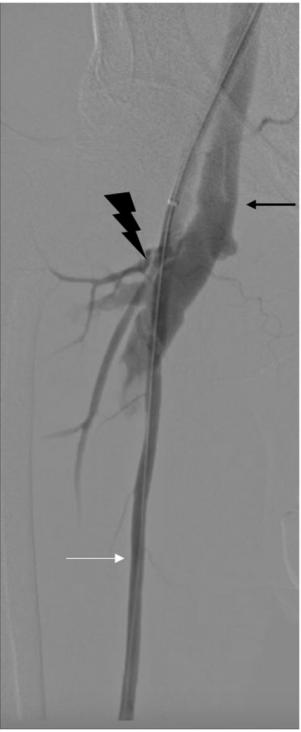

血管造影显示患者股总动脉和股总静脉之间有一个大的右侧股动静脉瘘。随后患者成功接受了经皮瘘管去除术,并在股总动脉植入了血管内支架(图2)。

图2,周围血管造影显示股动静脉瘘(白色箭头为股总动脉;闪电样标志为动静脉瘘;黑色箭头为股总静脉)。